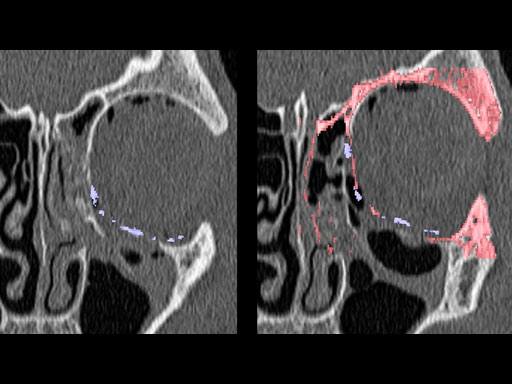

30-year-old male with fracture of left orbital floor and involvement of medial wall.

Case provided by Marc C Metzger, Freiburg, Germany

Fig 1 CT scan with fused image of virtual prebent orbital plate.